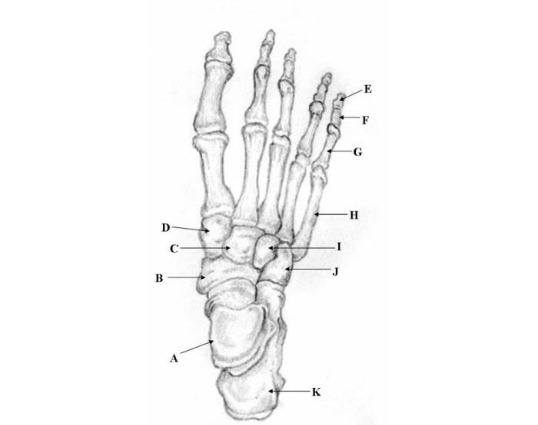

Two prompts were entered into ChatGPT (Prompt 1: “Make me a picture of human foot with the bones labeled”, Prompt 2: “Identify the structures labeled in this image”). Results of prompt 1, seen in figure 4, are that the generated image was detailed and visually appealing, correctly displaying a foot with visible bones as requested. However, the labeling is entirely inaccurate, with misspelled anatomical terms, misplaced labels, and several missing bones, including the phalanges of the 4th toe. The result of prompt 2 for the first illustrated image is 27% accurate with 3 of 11 bones accurately identified as shown in table 1. The result of prompt 2 for the second illustrated image is 57% accurate with 4 of 7 bones accurately identified as shown in table 2. The result of prompt 2 for the x-ray image is 0% accurate with 0 of 19 structures accurately identified as shown in table 3.

Prompt 1: “Make me a picture of human foot with the bones labeled”

ChatGPT Output:

The output from ChatGPT v4o of prompt 1 "‘Make me a picture of human foot with the bones labeled’ demonstrates a visually appealing and detailed depiction of a human foot with visible bones. However, the labeling is inaccurate, with anatomical terms misspelled, labels misplaced, and several key bones, such as the phalanges of the 4th toe, completely missing. Prompt 2 reveals varying accuracy between the 3 images used: 27% for the first illustrated image, 57% for the second illustrated image, and 0% accuracy for the x-ray image.